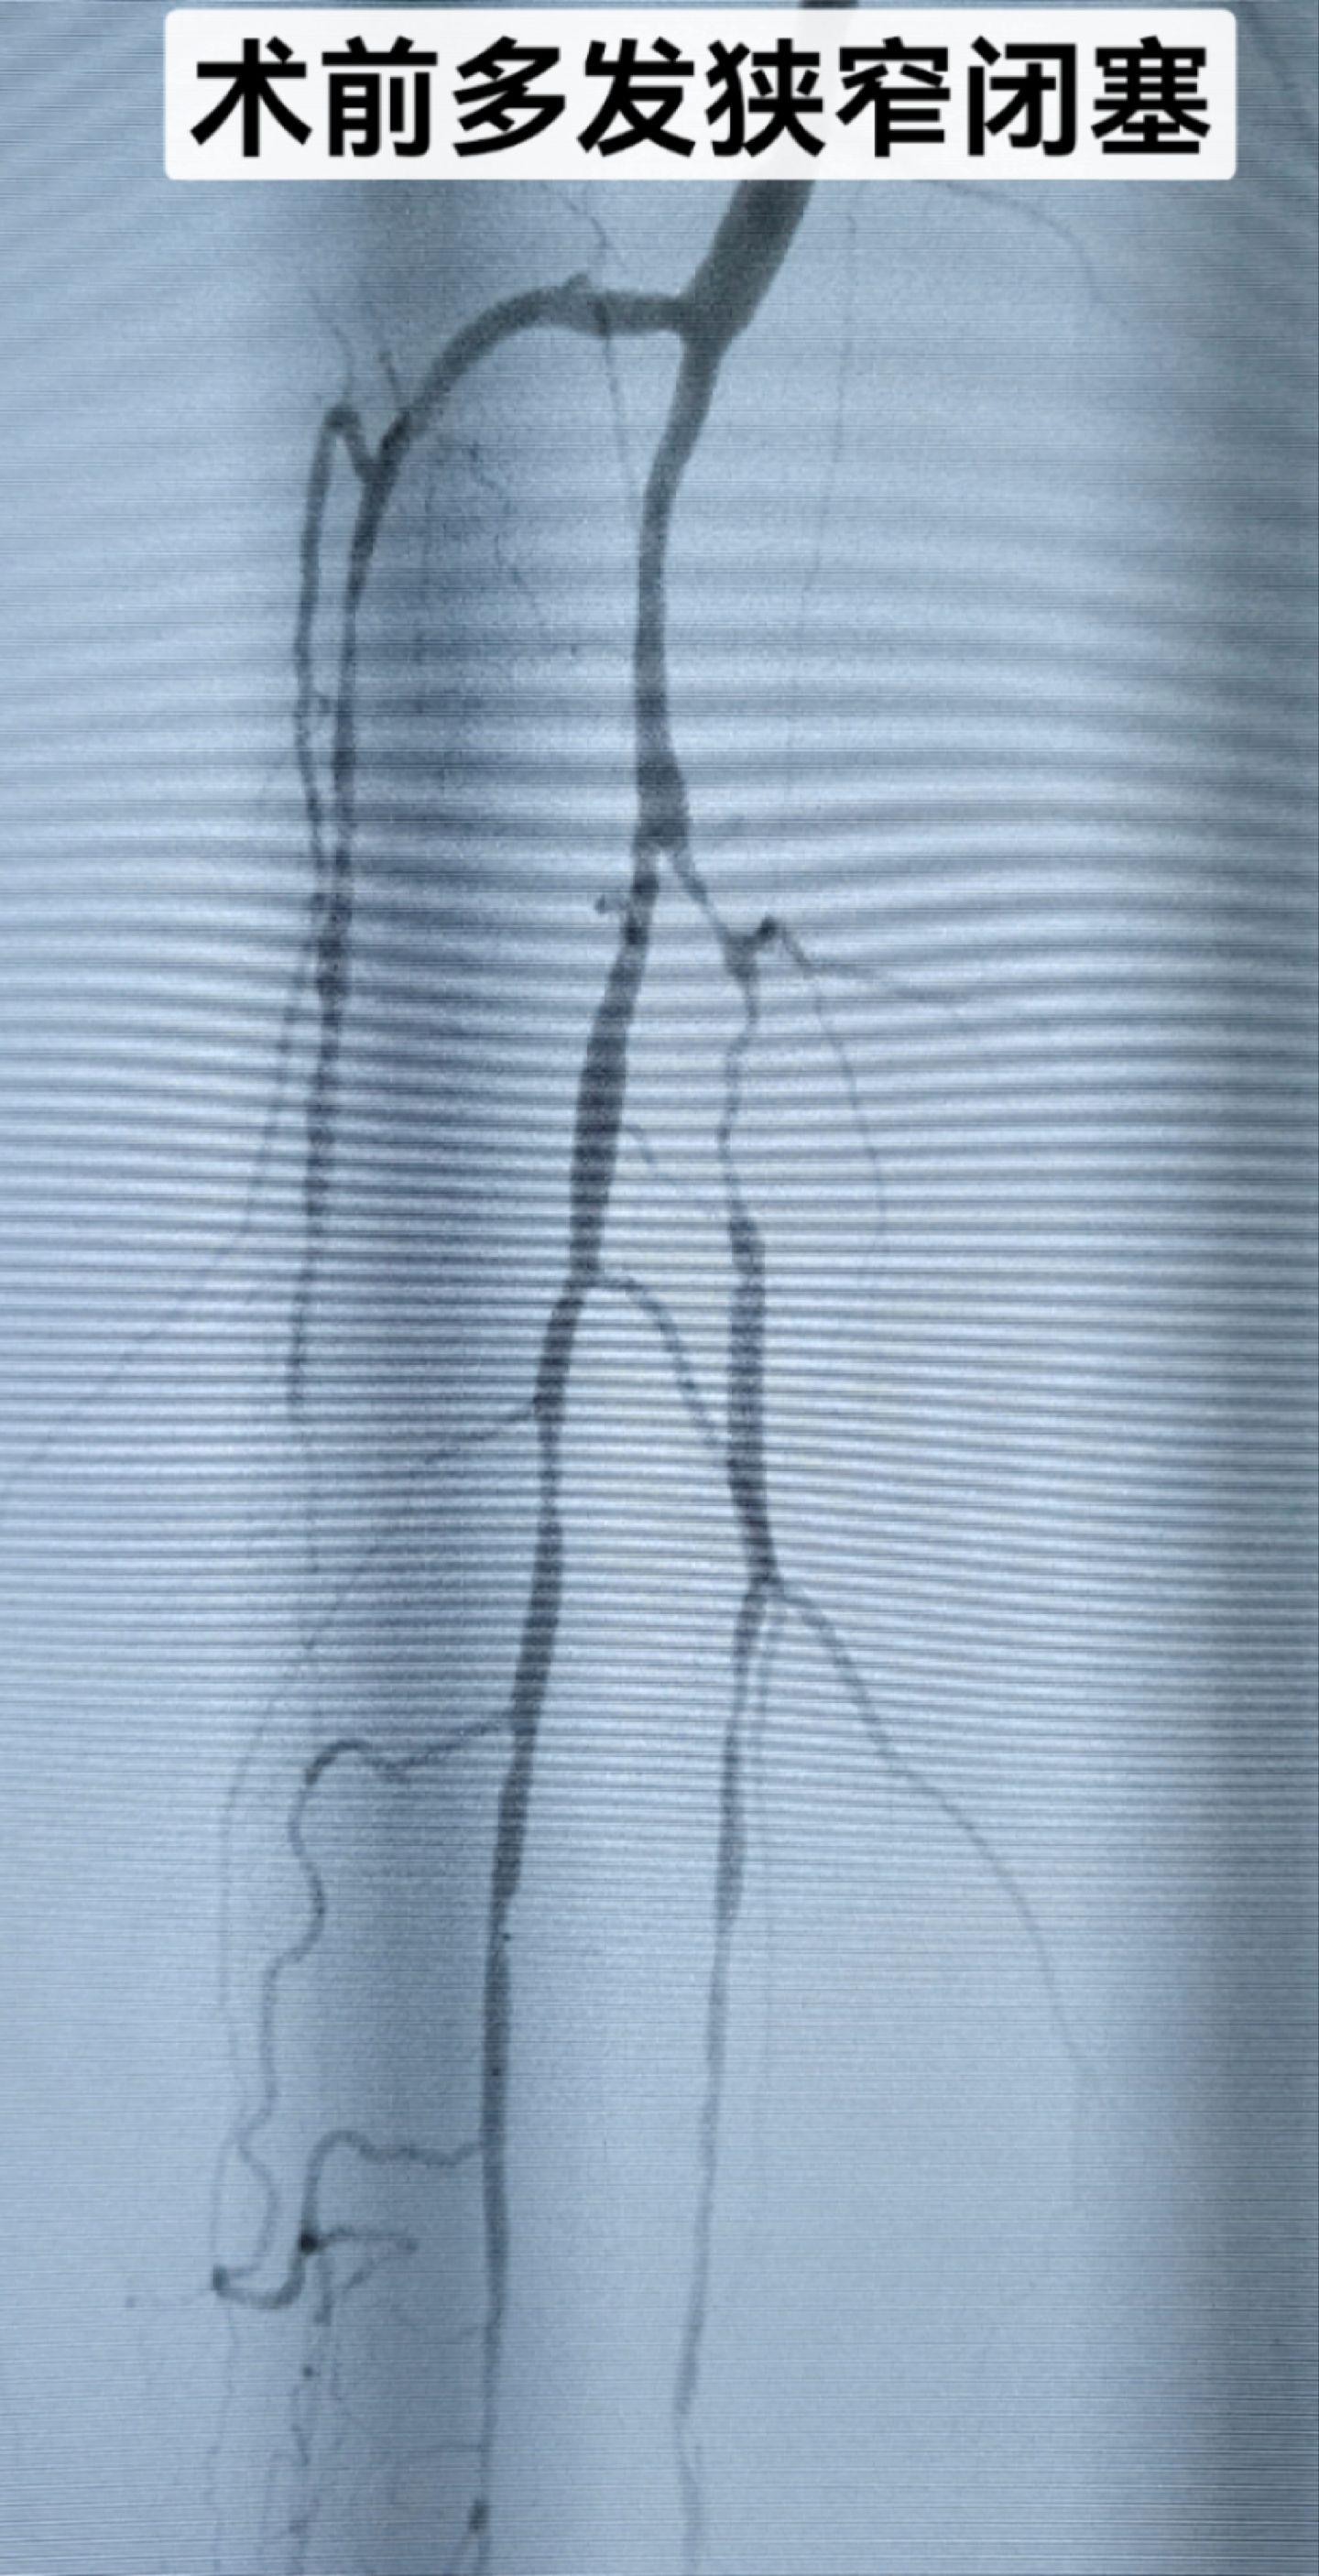

糖尿病足,反复下肢溃疡,膝下三条血管全部开通,保证血流,促进创面愈合